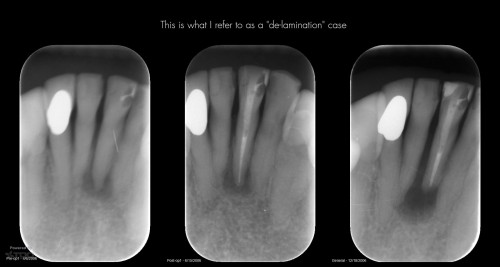

Suspected delamination case over 12 years

The patient is now 89. Looks like it’s time to do a root resection.